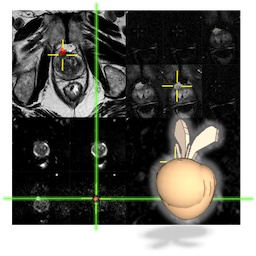

Vous retrouverez toutes les vidéos de cours, l’intégralité des cas cliniques dans une visionneuse DICOM en ligne, avec leur correction en vidéo, et une vingtaine en BONUS, soit plus de 55 cas cliniques !!!

C’est l’occasion de revoir PI-QUAL, PI-RADS et EPE, PRECISE, les compte-rendu structuré…et tellement d’autres détails indispensables.